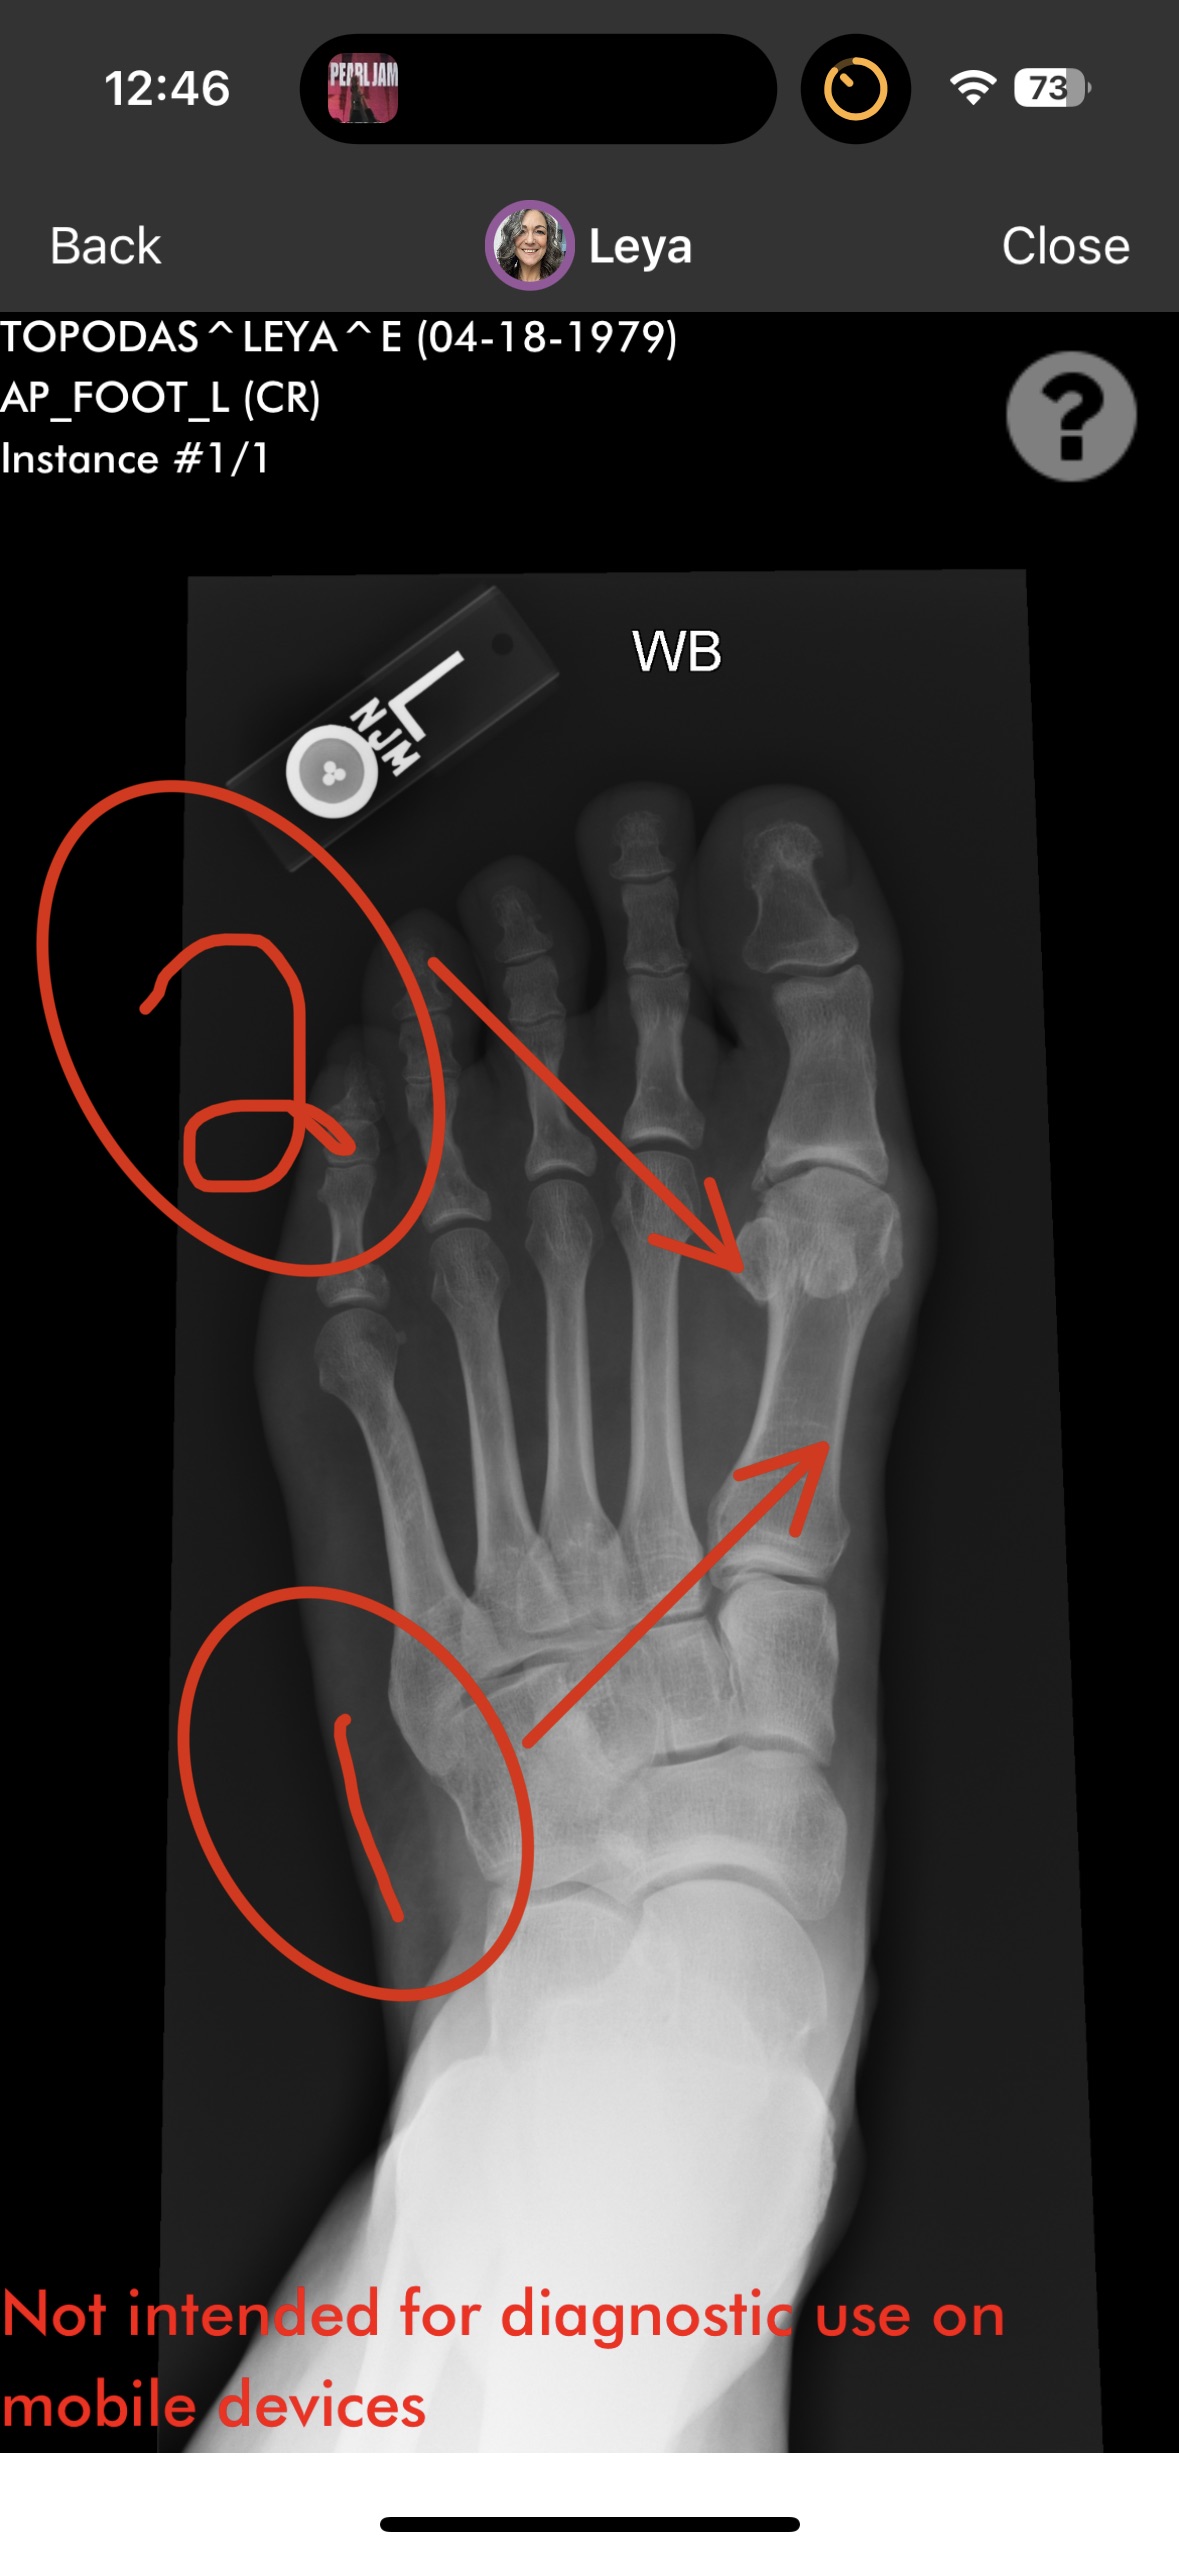

My decades-long year career of being on my feet and walking all over this city combined with a genetic predisposition has resulted in very severe and painful arthritis in my feet. I developed bone spurs in my metatarsophalangeal joint and lost cartilage. Known as hallux rigidus, my condition has limited my range of motion and affected my gait. I worked though the pain because I love what I do. About a year ago the pain was unbearable. I consulted an orthopedic surgeon who told me to quit bartending or have surgery.